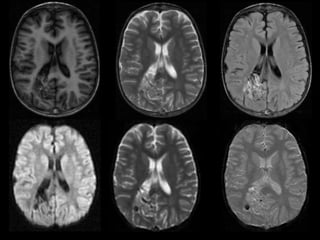

RMN DE CRÁNEO

20/06/2023

ADQUISICIÓN AXIAL

T1 T2 FLAIR

DWI ADC EG

ADQUISICIÓN AXIAL.

T1 CC

ANGIO TOF

3D

 Malformación arterio-venosa cerebral con

dilatación aneurismática de la vena de galeno vs

aneurisma de la vena de galeno vs fístula

arteriovenosa pial. Escala de Spetzler – Martin 5

puntos.

 Pansinusopatía.

 Hipertrofia turbinal.

CONCLUSIONES:

Hallazgos en RM

Potenciación en T1

o La señal varía dependiendo de la velocidad

y la dirección del flujo, y de la presencia o

antigüedad de la hemorragia.

o Masa/conglomerada : «panal» de vacíos de

flujo .

Potenciación en T2

o Red de vacíos de señal serpenteantes, en

«panal de abejas» .

o Hemorragia variable.

o Tejido cerebral escaso o inexistente en el

interior del nido.

FLAIR

o Vacíos de flujo ± señal elevada circundante

(gliosis)

En T1 con contraste (en T1 C)

o Realce muy marcado del nido y las venas de

drenaje

o El flujo rápido puede no mostrar realce (<<vacío

de flujo»)